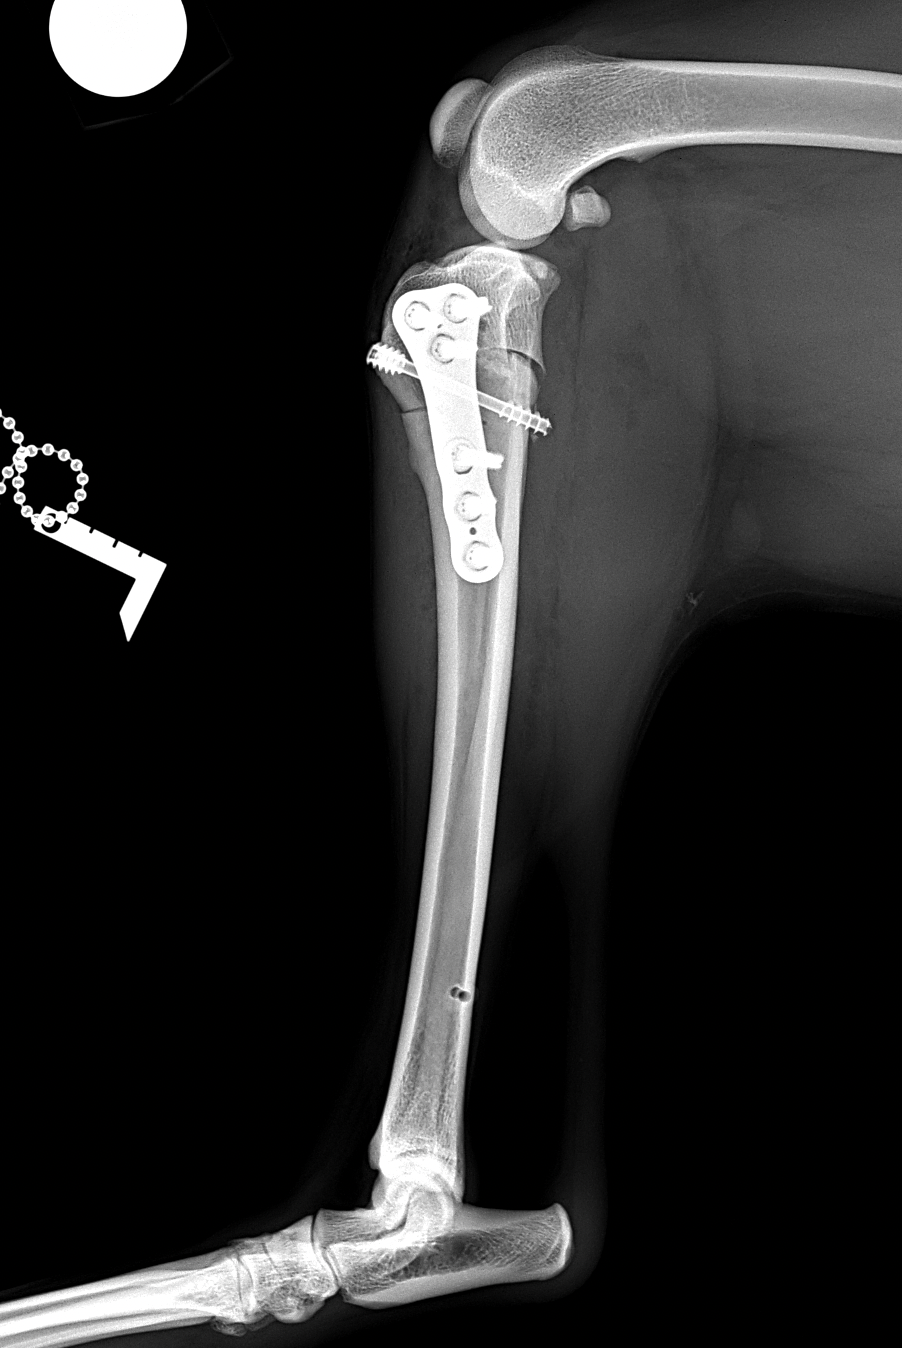

前十字靭帯部分断裂の患者さんに対して、CORA Based Leveling Osteotomyで対応しました。(2.7 Rita CCWO Plate+3.5 Locking Screw+4.0 Head Less Compression Screw) 。しばらく安静が必要です。